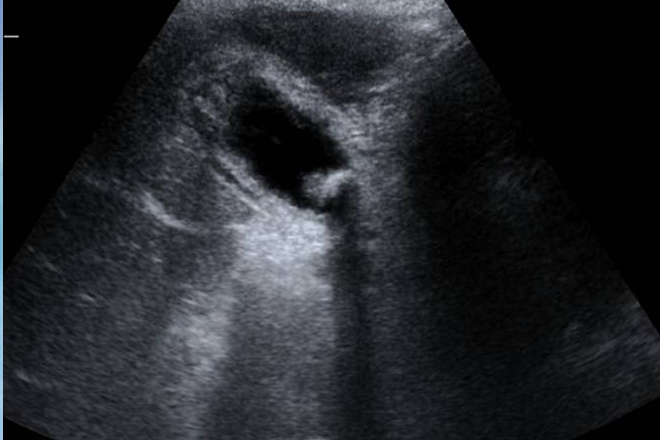

En este estudio se destaca la importancia de la litiasis biliar en pacientes con preeclampsia severa, un tema poco explorado hasta ahora. Aunque el dolor abdominal, las náuseas y los vómitos son síntomas clásicos de la eclampsia inminente, también pueden indicar la presencia de litiasis biliar. Esta condición es una de las principales causas no obstétricas de hospitalización en mujeres embarazadas o en el posparto inmediato. A pesar de que el diagnóstico se realiza clínicamente, la ecografía es fundamental para confirmar o descartar la eclampsia, ya que se ha reportado una frecuencia del 4.3% de pacientes con preeclampsia que también tienen litiasis biliar.

Las pacientes se dividieron en dos grupos según los hallazgos ecográficos: Grupo A (sin litiasis) y Grupo B (con litiasis). En el Grupo B se incluyeron casos de lodo biliar, cálculos únicos, múltiples o vesícula calcificada. Se analizaron datos maternos como edad, paridad, peso, semanas de gestación, síntomas abdominales, resultados de laboratorio y días en cuidados intensivos. En cuanto al feto, se evaluó el peso, la edad gestacional, calificación de Apgar al minuto y a los 5 minutos, supervivencia y mortalidad neonatal.

De los 141 pacientes, 120 pertenecían al Grupo A y 21 al Grupo B. Se investigó hipertransaminasemia en el 88.6% de los casos, dolor abdominal de origen hepático en el 9.2%, signos clínicos de colecistitis aguda en el 1.4% y se verificó la presencia de litiasis ya conocida. Entre los hallazgos ecográficos, se identificaron cálculos en 19 casos, de los cuales 12 eran únicos y 7 múltiples. Nueve casos presentaron lodo biliar, la mayoría en el Grupo A, y tres casos mostraron pólipos vesiculares, excluyendo la coexistencia con litiasis. No se observaron cambios significativos en el diámetro del colédoco.

Comentario: Es fundamental considerar la litiasis biliar como un posible diagnóstico diferencial en pacientes con preeclampsia, dada la similitud de síntomas con la eclampsia. El diagnóstico temprano es crucial debido a la urgencia que esta condición representa. Además, la ecografía es una herramienta esencial para el diagnóstico, junto con la evaluación del feto para determinar su estado de salud.